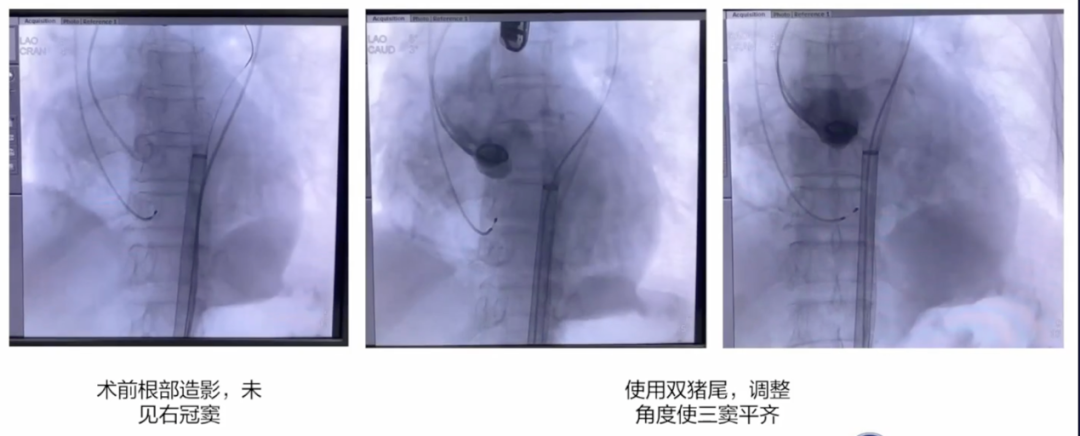

本例患者78岁男性,重度AS并合并多瓣膜钙化,PGmax达112mmHg。CT评估提示Type-1二叶瓣,左右融合伴极重度钙化,延伸至升主动脉;瓣环与流出道均有钙化沉积,手术风险高。

经全面评估,最终拟经股入路,采用20/22 mm球囊预扩张后,植入VenusA-L 29mm瓣膜,备用32 mm瓣膜。术后造影与超声评估均显示瓣膜展开理想,无明显反流,手术成功。

小球囊预扩张

20mm球囊预扩张

双平面造影确认植入位置

释放完成

球囊后扩后,超声确认植入位置合适,形态满意,造影未见反流